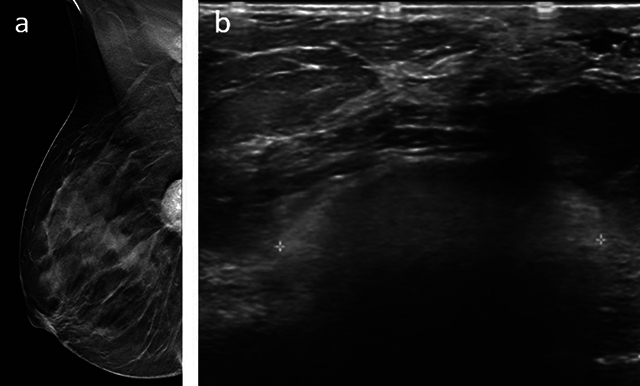

Silicone gel-filled breast implants are widely used for breast augmentation and reconstruction after mastectomy. However, there are some known complications associated with silicone implants: Leakage and migration of silicone particles from the implant cause a granulomatous reaction. Granulomas may present as masses with features of malignancy on breast MRI. We present a case of a giant breast siliconoma in a woman who had undergone reconstruction with breast prostheses, which were surgically removed because of rupture 8 years ago. Teaching point: Despite increasingly efficient diagnostic tools, siliconoma diagnosis remains challenging.

硅凝胶填充乳房假体广泛用于乳房切除术后的隆胸和重建。不过,硅胶假体也有一些已知的并发症:硅胶微粒从植入物中渗漏和迁移会引起肉芽肿反应。肉芽肿在乳腺核磁共振成像中可能表现为具有恶性肿瘤特征的肿块。我们介绍了一例巨大乳腺硅胶瘤病例,患者曾接受过乳房假体重建手术,8 年前因假体破裂而被手术取出。教学要点:尽管诊断工具越来越有效,但硅胶瘤的诊断仍然具有挑战性。